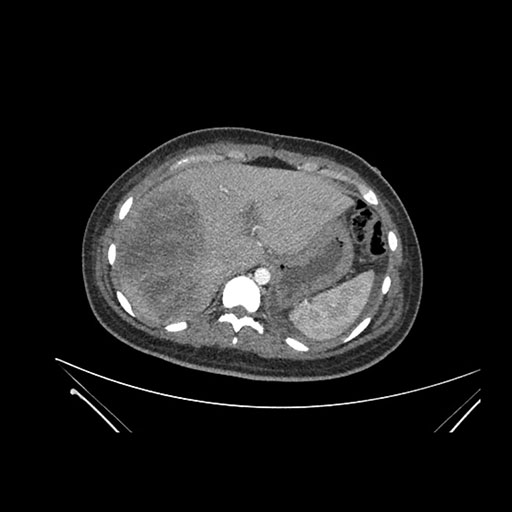

Imaging Analysis

Look through the patient's CT scan to identify any areas of concern for the necessary procedure.

Coronal Venous

Based on initial findings, which issue(s) would you be most concerned about?